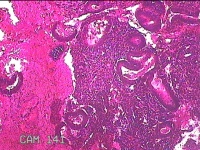

宫腔内容物

性别

女

年龄

48岁

临床诊断

1.异常子宫出血 3.慢性宫颈炎 2.宫颈赘生物性质待查

一般病史

月经量增多16年。

标本名称

大体所见

灰白暗红色不规则碎组织1.5x1.3x0.3cm一堆。

图1